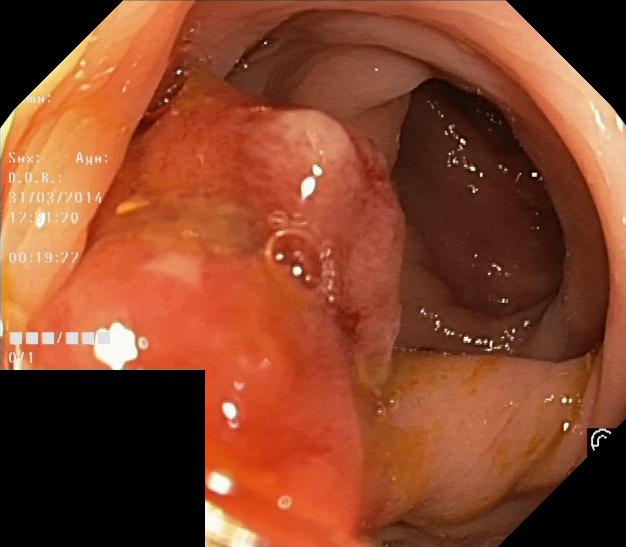

We have used a polyp dataset published with HyperKvasir dataset [51], which consists of polyp findings extracted from endoscopy examinations. HyperKvasir contains polyp images with corresponding segmentation masks annotated by medical experts. We use only this polyp dataset as a case study because of the time and resource-consuming training process of the SinGAN-Seg pipeline. However, the SinGAN-Seg model and pipeline can be used for any segmentation dataset.

A few sample images and the corresponding masks of the polyp dataset in HyperKvasir are shown in Fig 2. The polyp images are RGB images. The masks of the polyp images are single-channel images with white () for true pixels, which represent polyp regions, and black () for false pixels, which represent clean colon or background regions. In this dataset, there are different sizes of polyps. The distribution of polyp sizes as a percentage of the full image size is presented in the histogram plot in Fig 3, and we can observe that there are more relatively small polyps compared to larger polyps. Additionally, a subset of this dataset was used to prove that the performance of segmentation models trained with small datasets can be improved using our SinGAN-Seg pipeline, and the whole dataset was used to show the effect of using SinGAN-Seg generated synthetic images instead of a large dataset which has enough data to train segmentation models. In this regard, this dataset was used for two purposes: